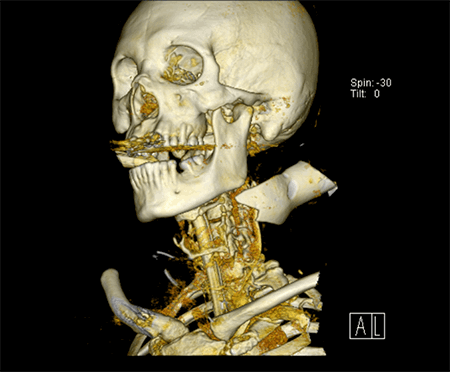

On arrival, the patient was talking and protecting his airway. He was tachycardic with a heart rate of 140 bpm. He was hypotensive with systolic blood pressure of 70 mmHg. His Glasgow Coma Scale was 9. The patient was resuscitated according to Advanced Trauma Life Support protocol with blood products as well as minimal crystalloid with the assumption that the patient had bled significantly on scene. The patient responded appropriately to minimal volume resuscitation evidenced by the stabilization of his vital signs. He was intoxicated, agitated and deemed to be a threat to himself and others, and was therefore intubated. Removal of the foreign body was thought to be best suited in the operating room in a well-controlled environment based on the abutment of the object to the surrounding vascular and nervous structures as well as to ensure the retrieval of all foreign material. It is also important to note the need for personal protection and safety of the surgical team members when dealing with sharp foreign bodies and therefore this controlled environment would be optimum. Given that he became hemodynamically stable with minimal volume resuscitation, he was taken for a CT angiogram (Figure 2 and Figure 3), which revealed the distal tip of a glass beer bottle closely approximating the posterolateral internal jugular vein without evident extravasation and no evidence of trauma to any other surrounding vasculature. The foreign body extended through the anteromedial aspect of the left sternocleidomastoid muscle and entered the left posterolateral paraspinal musculature.

Figure 3. CT 3 dimensional reconstruction.